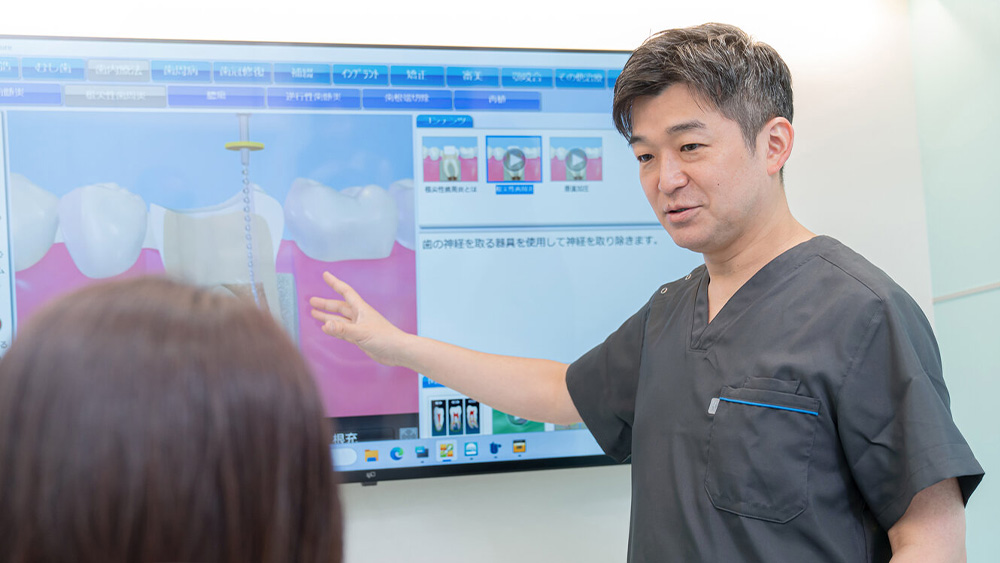

患者さんと共に状態を「目で見て」確認する

ご自身の歯の内部がどのような状態になっているのか、治療がどのように進んでいるのかは、なかなかイメージしにくいものです。

当院では、口腔内カメラで撮影したお口の中の様子を、診療台の大きなモニターに映し出し、患者さんと一緒に確認しながらご説明しています。

治療計画の説明

精密検査の結果をもとに、現在の歯の状態と必要な治療についてご説明いたします。

治療方法を分かりやすくイメージしていただくために、3Dアニメーションなども用いて、複数の選択肢とそのメリットをお伝えします。